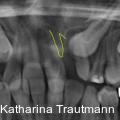

Die interdisziplinäre Zusammenarbeit spielt in der modernen Kieferorthopädie eine zentrale Rolle, insbesondere bei komplexeren Behandlungsfällen, die über das alltägliche Behandlungsspektrum hinausreichen. Fotos: © Dr. Johanna Katharina Trautmann